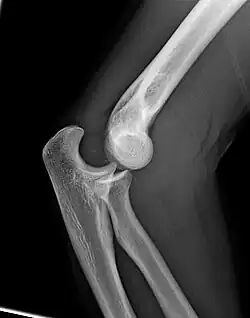

Articulación del codo

En anatomía, la articulación del codo es la que une el brazo con el antebrazo, conectando la parte distal del hueso húmero con los extremos proximales de los huesos cúbito y radio. La articulación principal que constituye el codo se denomina humero radio-cubital y puede dividirse en dos partes bien diferenciadas: la articulación humero-radial y la humero-cubital. Por otra parte, el cúbito y el radio forman también una articulación entre sí en las proximidades del codo, la cual se denomina articulación radio-cubital proximal. Los extremos óseos se conectan entre sí por un conjunto de ligamentos que contribuyen a su fijación y están rodeados por una estructura común que se llama cápsula articular, en cuyo interior se encuentra el líquido sinovial.[1]

El codo está formado por tres articulaciones diferentes: la humero-radial que une el húmero con la cabeza del radio, la humeral-cubital que une el cúbito con el húmero, y la radio-cubital que establece la unión entre radio y cúbito. Las tres están englobadas en la misma cápsula articular.